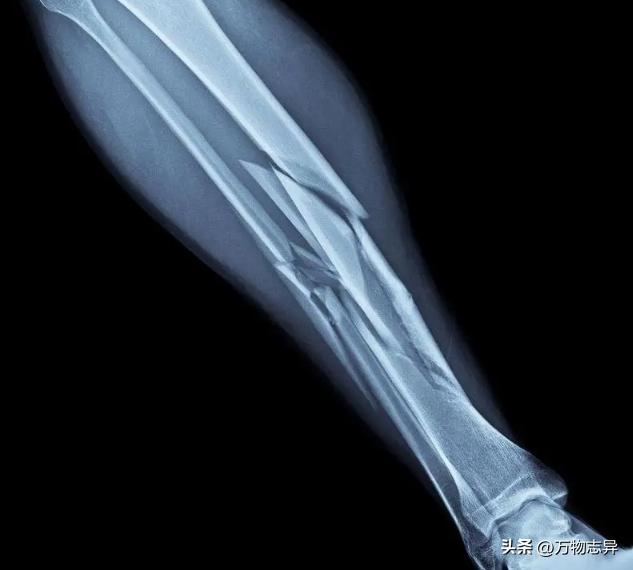

“你们看这个。”医生说,指着电脑屏幕上的一个图像。

我和老公凑过去一看,发现是一个X光片。上面显示了婆婆的腿骨的情况。我们看到她的腿骨不仅裂了两处,而且还有一处是断了的。

“这意味着她的伤势比我们预想的要严重得多。”医生说,“我们需要用更复杂的手术方法来治疗她。”

“是的,我们需要用钢板和钢钉来固定她的骨头,并且还要做骨移植。”医生说。